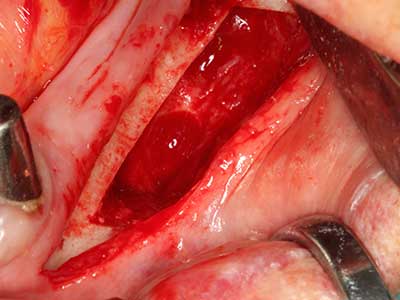

Fig. 18: preparazione di una copertura corticale con sega piezoelettrica per osso (Piezomed, W&H).

Fig. 19: sito chirurgico dopo neurolisi e rimozione dell'osteoma.

Fig. 20: la copertura ossea rimossa viene riadattata e fissata con una vite per osteosintesi (KLS Martin, Tuttlingen).